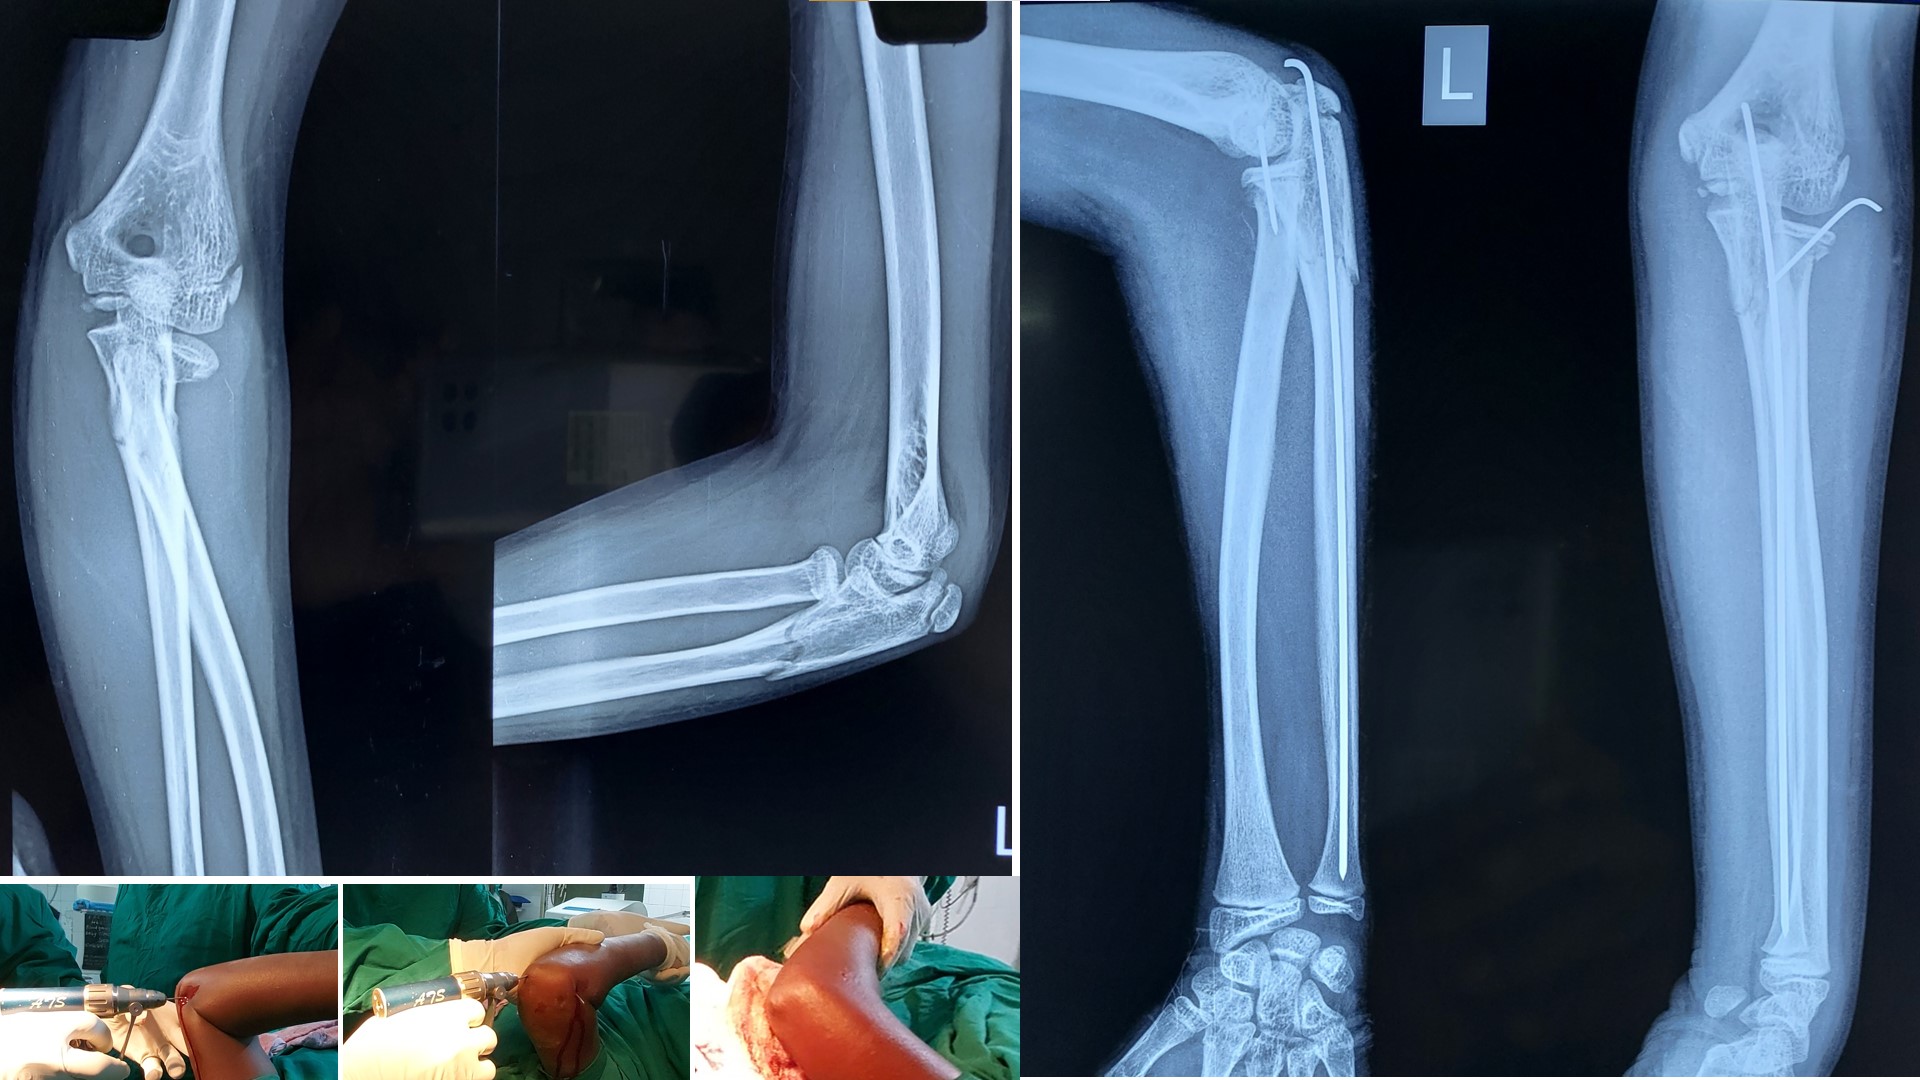

FOREARM FRACTURES